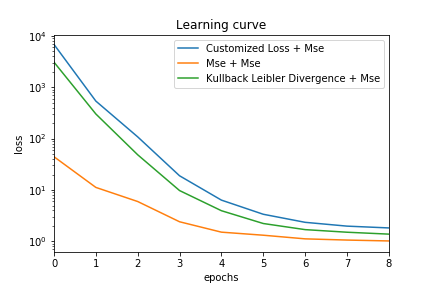

For the unsupervised learning part, the objective is to minimize the loss of the model which is, in our case, a customized loss that combines Mean Square Error (MSE), -regularization and Kullback Leibler (KL) divergence. The use of such a loss allows avoiding overfitting (-regularization in order to decrease the magnitude of the weights) as well as learning higher representations of the Region of interest (sparsity constraints using KL divergence).

Customizing the loss of our neural network can totally change the performance of our approach in both ways [9]. Let’s recall that the method uses a customized loss for the two stacked autoencoder (weighting between Mean Square Error (MSE), regularisation and Kullback-Leibler (KL) divergence) in the unsupervised learning step and a regular MSE for the last fully connected layer in the supervised learning step. We test another alternative where all the losses are MSE and plot the contours from the manually segmented LV, the prediction with and without active contour models in Figure 6. As we can see, the contour is smoother and seems to fit the ground truth while having a meaningful shape (not shrinking or leaking or irregularities).